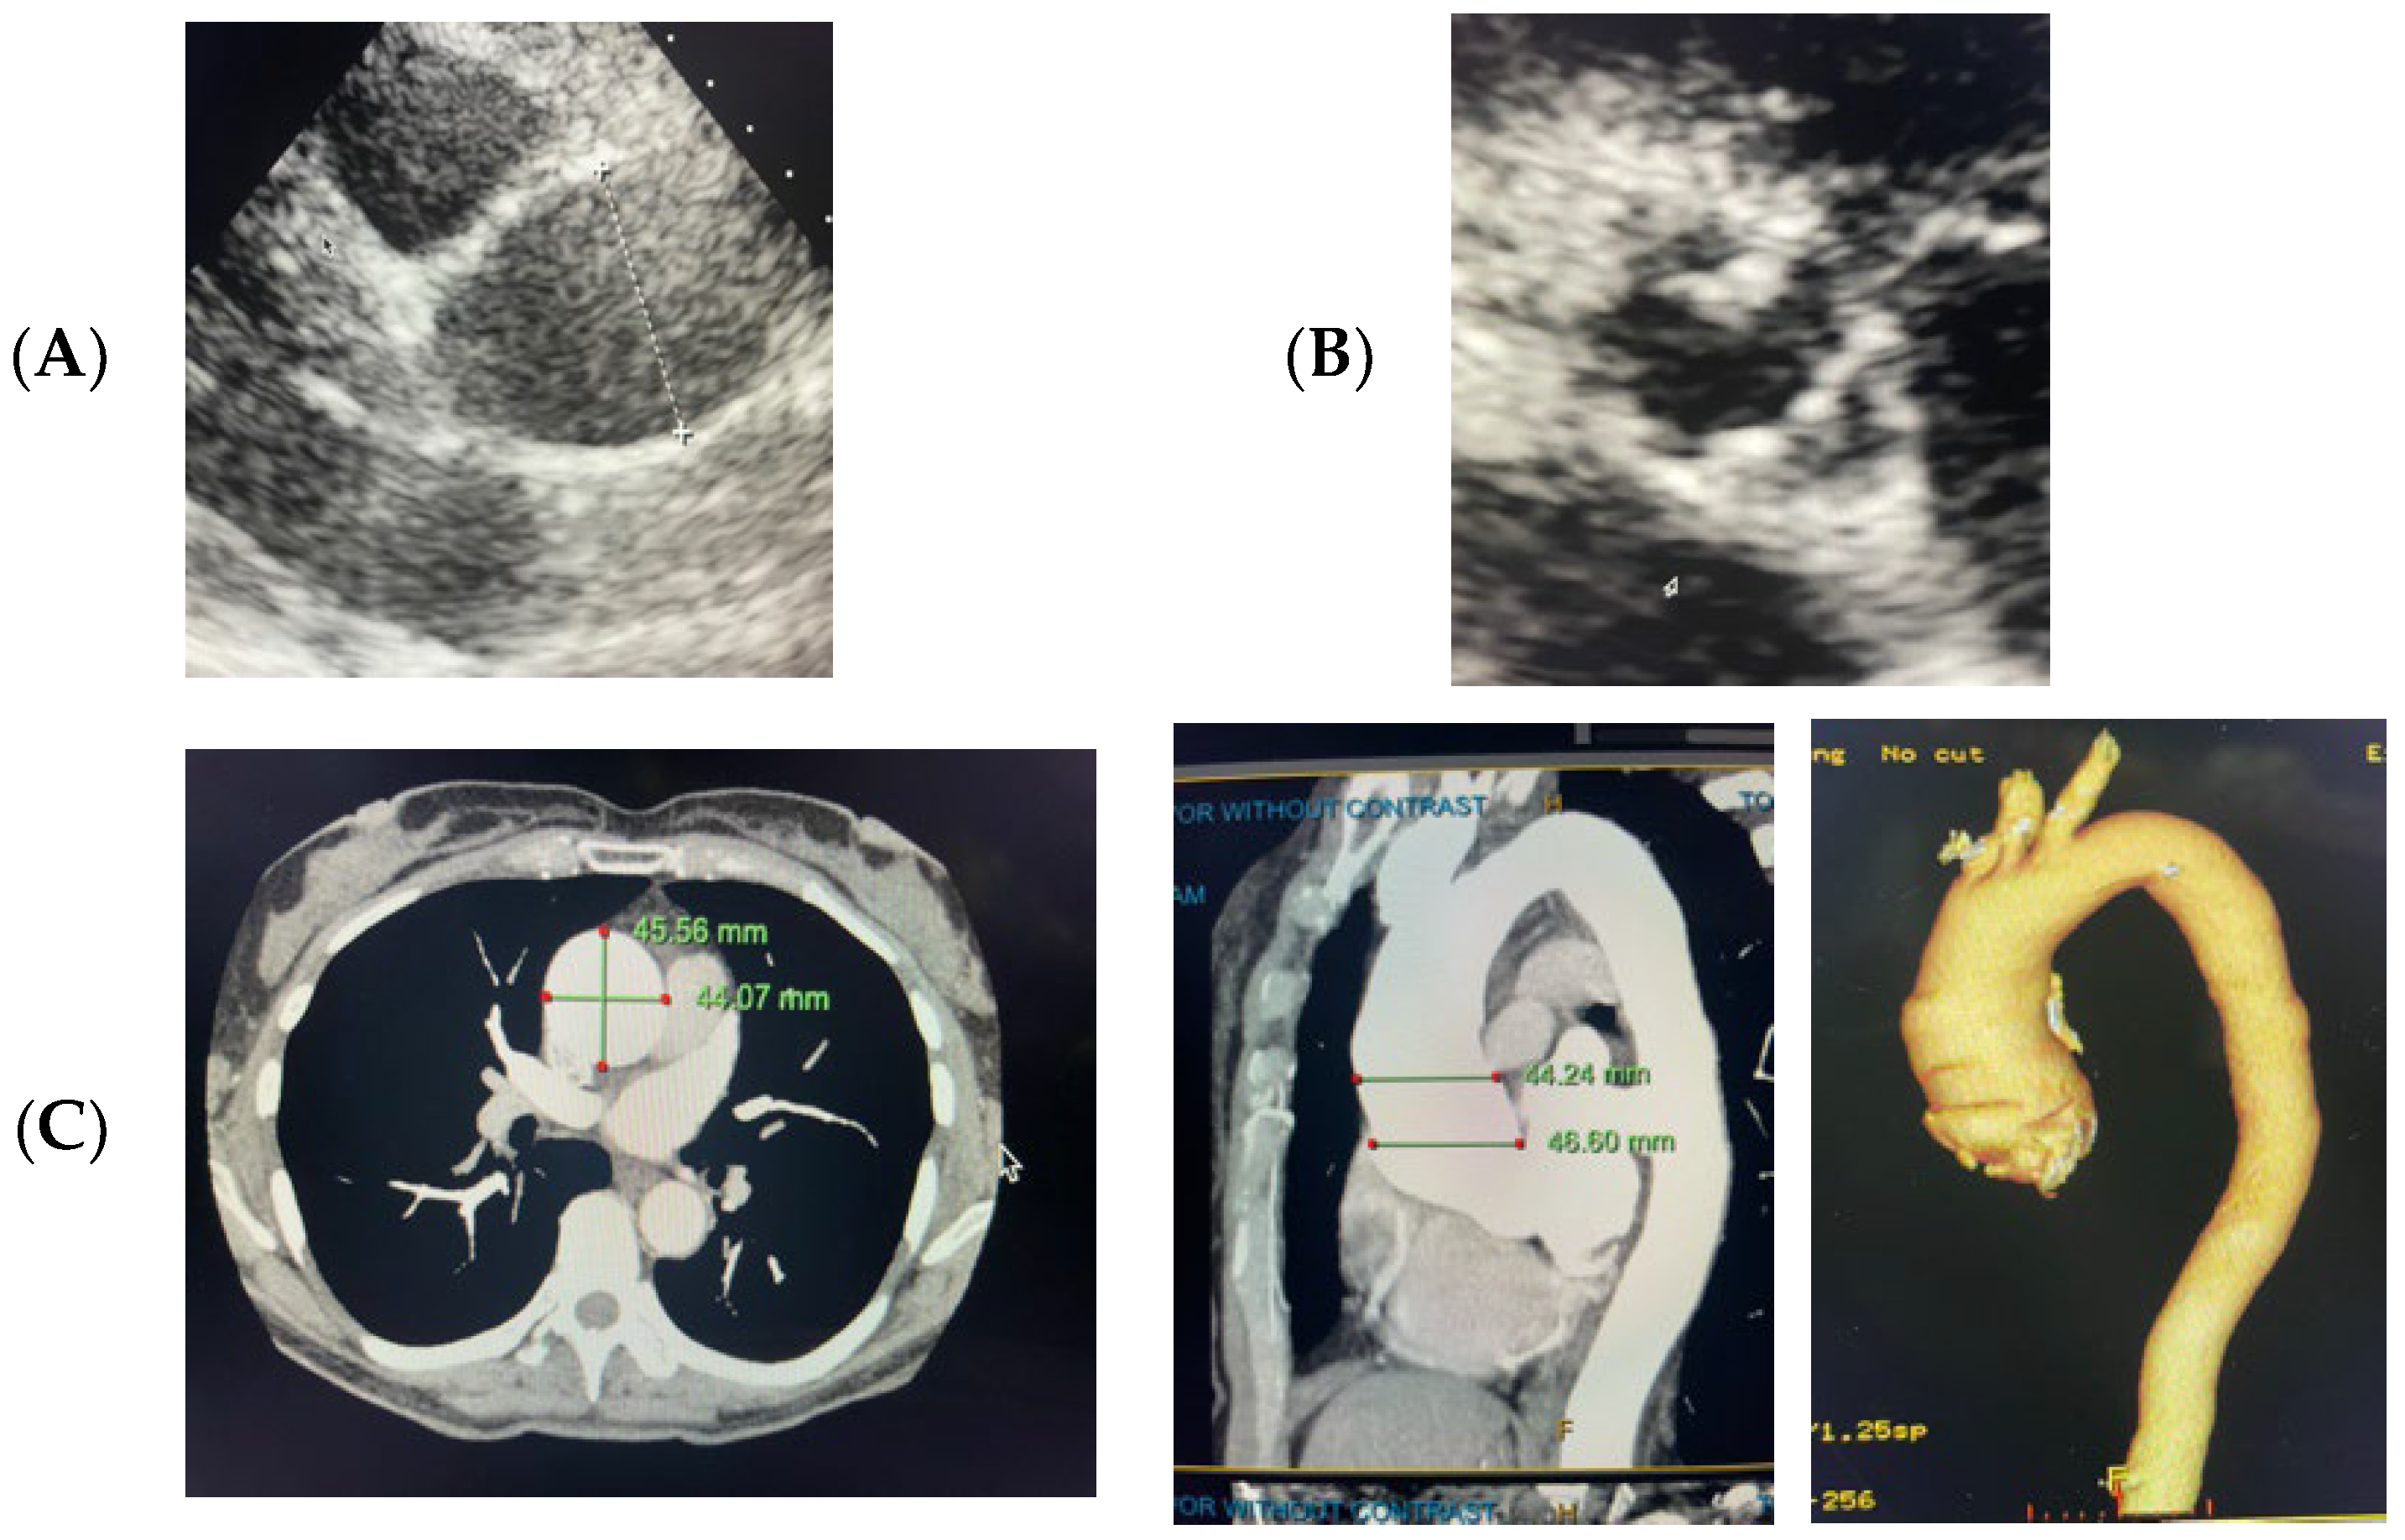

2.1. Case 1

2.2. Case 2